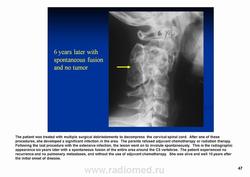

Телеангиэктатическая остеосаркома относится к остеолитическим вариантам обыкновенной интрамедуллярной остеосаркомы и содержит кистовидные сосудистые полости, разделенные тонкими костными перегородками. В некоторых случаях эта опухоль симулирует аневризматичесую костную кисту. Частота такого варианта составляет 0,4—12 % от общего числа остеосарком. Патологический перелом к моменту диагностики встречается более чем у 25 % больных, тогда как лиц с обыкновенной остеосаркомой — не более чем 5 %. У пациентов старшей возрастной группы, а также лиц с поражением костей осевого скелета развитие телеангиэктатической остеосаркомы происходит на фоне болезни Педжета. Макроскопически эта опухоль имеет вид то крупного сгустка крови или некротической массы, то многокамерной кисты, содержащей жидкую кровь, как это бывает в аневризматической костной кисте.

Рентгенологически выявляют метафизарную локализацию, полностью литическое поражение без признаков оссификации, часто интенсивное вздутие кости и её деструкцию, формирование мягкотканого компонента, иногда периостальную реакцию.